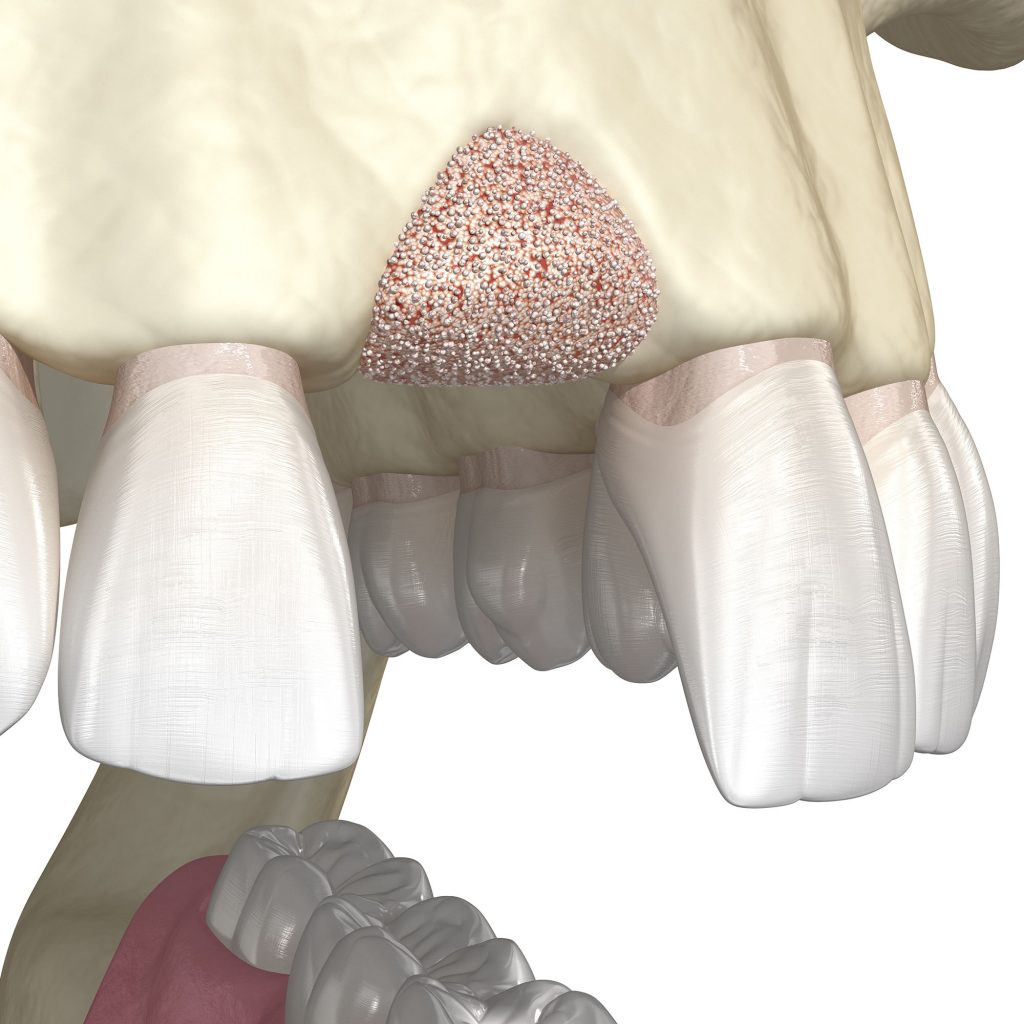

Mivel a műgyökeret az állcsontba ültetjük be, az implantáció alapfeltétele a megfelelő csontkínálat. Mivel a fogvesztést elszenvedett terület csontozata fokozatosan leépül, elsorvad, idővel eléri azt a szintet, amikor már nincs elegendő mennyiségű csont egy műgyökér beültetéséhez. A csontpótlásra többféle módszer létezik: az arcüregemelés (sinus lift) és az állcsontgerinc pótlás (augmentáció). Az eljárás kisebb csonthiány esetén ez az implantátum beültetésével egy időben elvégezhető, nagyobb csonthiánynál azonban hónapokkal a beavatkozás előtt meg kell ejteni.